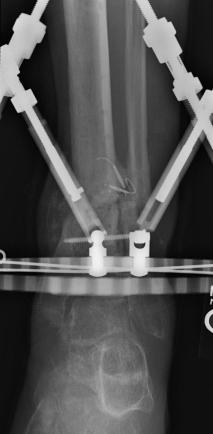

Postoperative (13th) images of left ankle

The image(s) displayed here were created following Liam's 13th surgery which was performed by Dr. Saunders. After a few hiccups getting

the surgery scheduled, Liam spent most of the September 13th afternoon in his 13th surgery. ;-) The surgery lasted about 5 hours and according

to the doctor, it was a good surgery. The 1st photo shows the new frame bracing that holds Liam's ankle together. The next series of photos show

various angles of the ankle and the rods that go from the frame into and through the left ankle. There was some concern that the swelling would

burst and allow for infection. Looks like we are now past that concern. Liam is still on antibiotics to ward of potential infection. The flesh

images show how the skin reacts to having the leg adjusted by the brace. The doctor has had to cut the skin to allow the rods to move freely.